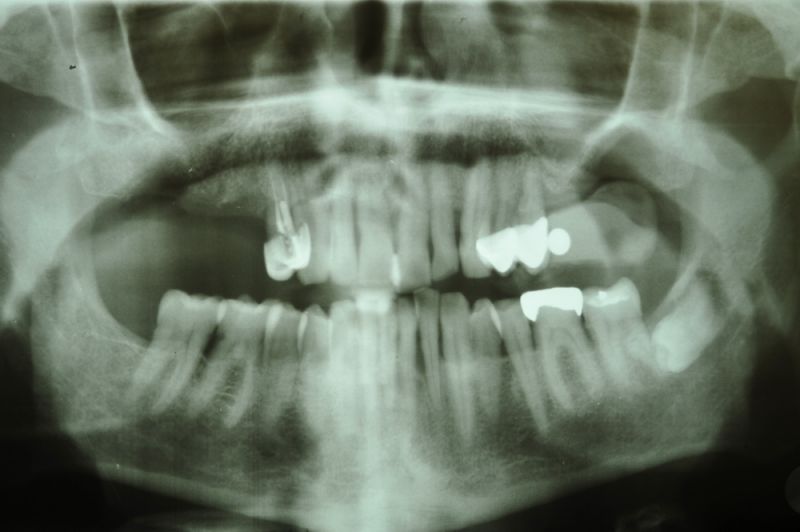

73 jähriger CMD-Patient im Recall

Der Patient hat vor 5 Jahren eine äußerst umfangreiche und komplexe CMD-Behandlung abgesclossen und befindet sich seitdem in einem engmaschigen vierteljährlichen Recall!

Seit 5 Jahren ist der Zustand des Patienten vollkommen unverändert!

Die aktuellen Taschentiefen liegen bei 2 Millimeter! Auch im Bereich der Implantate!

Das Allerwichtigste bleibt aber der engmaschige, vierteljähliche Recall, der aus mehr besteht, als nur einem Zahnsteinentfernen! Wichtig ist die fortlaufende Dokumentation der verschiedenen Parameter der parodontalen Gesundheit und genauso wichtig eine Röntgenkontrolle etwas alle ein bis eineinhalb Jahre.